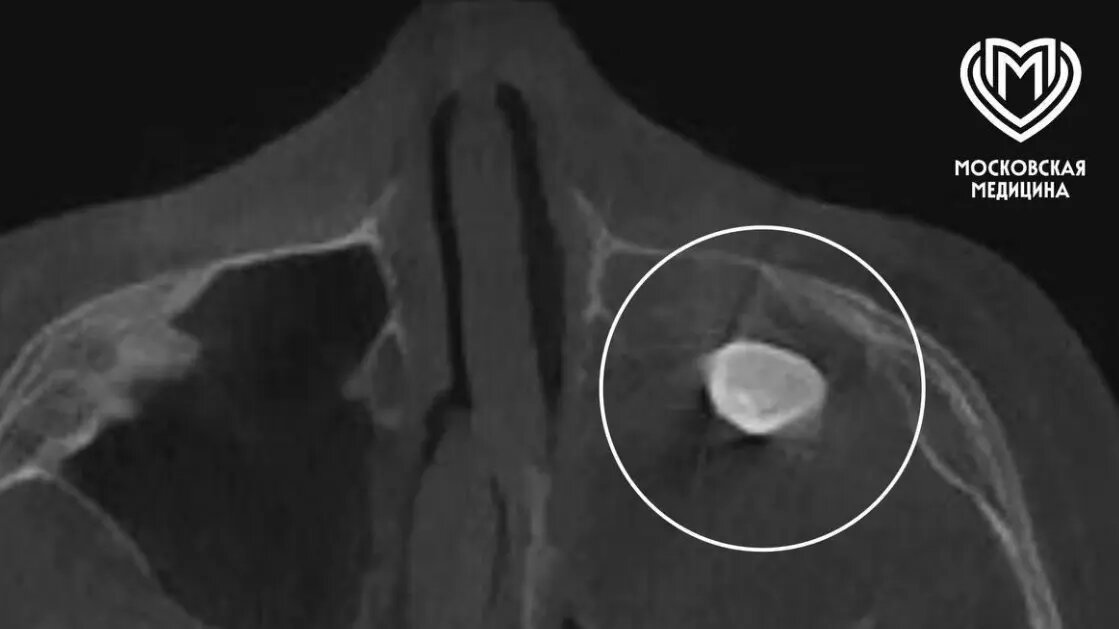

Юный пациент почувствовал дискомфорт из-за заложенности носа и асимметричной формы лица, поэтому семья обратилась за помощью. В одной из частных клиник врачи выявили наличие необычного зуба в гайморовой пазухе, но родители мальчика приняли решение получить дополнительное мнение от профильных экспертов Филатовской детской больницы. Коллектив медицинского учреждения провёл тщательное обследование, чтобы точно определить объем и сложность предстоявшего вмешательства.

Современные методы помощи детям

Врачи собрали консилиум, результатом которого стало решение о необходимости операции по Колдуэллу-Люку. Исключительный опыт и слаженные действия хирургов позволили успешно провести деликатную процедуру — во время хирургического вмешательства специалисты обнаружили новообразование, внутри которого и был обнаружен образовавшийся зуб. Благодаря профессионализму и внимательному подходу медиков, проблема мальчика была полностью решена, а восстановление проходит успешно.